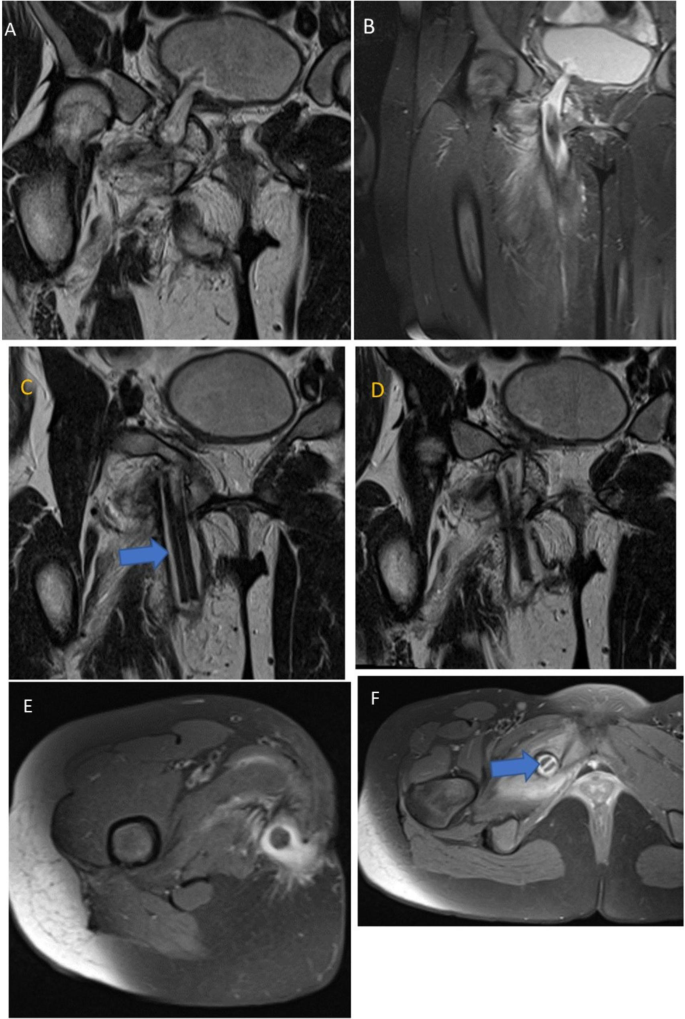

Рентгенография костей таза не выявила отклонений. В свою очередь, МРТ таза показала свищевой ход длиной около 10 см, в котором находилось инородное тело, проникающее в правую боковую стенку мочевого пузыря. Оно проходило через гребенчатую, длинную, короткую и большую приводящие, тонкую мышцы бедра, образуя везико-кожный свищ (рис. 2).

Рисунок 2. МРТ-снимки таза и верхней части правого бедра, на которых заметен свищевой ход длиной 10 см с инородным телом, проникающим в правую боковую стенку мочевого пузыря (A,B). Инородное тело проходит через внутреннюю и наружную запирательные мышцы, большую приводящую и тонкую мышцы бедра и выходит с внутренней стороны правого бедра (D,E). Также заметно инородное тело в свищевом ходу (E, F; синяя стрелка).